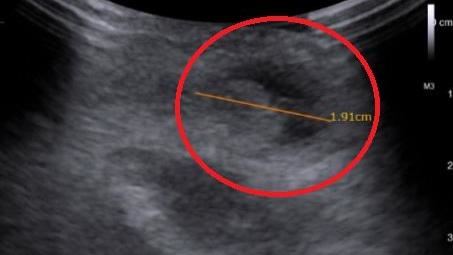

▲5歲男童長期不明原因肚子痛,經醫師檢查診斷是兒童腹股溝疝氣。(圖/烏日林新醫院提供)

▲▼5歲男童罹患腹股溝疝氣,導致睪丸上方出現2公分的腸子脂肪腫塊,經手術縫合約1周痊癒。(圖/烏日林新醫院提供)

男童媽媽表示,兒子從2歲開始就經常莫名肚子痛,吃了軟便劑、浣腸幫助排便也沒效,直到幼兒園進行健康檢查時,發現左邊睪丸上方有腫塊,才帶兒子到醫院就醫,醫師進行觸診、超音波檢查,發現底下有近2公分的腫塊,經診斷為兒童腹股溝疝氣,才導致肚子疼痛。